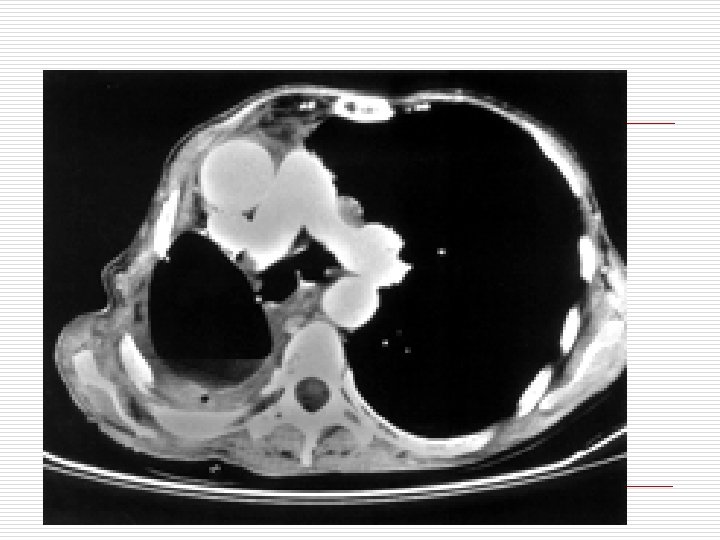

Diagnosis o X- ray chest: pleural effusion pyopneumothorax thickened pleura crowded ribs o CT chest: confirm diagnosis thickened pleura complications o Chest sonography: fluid collection loculations

Chronic Empyema